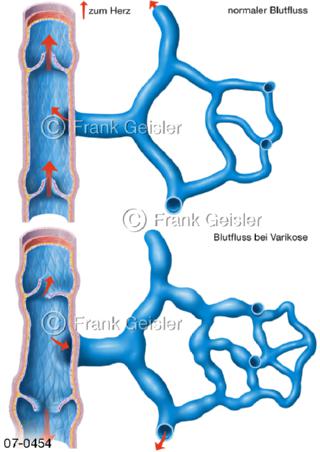

Bildergalerie Herz, Blutkreislauf

Bilder zu Herz, ein muskuläres Hohlorgan, das den menschlichen Körper durch rhythmische Kontraktionen mit Blut versorgt und dadurch die Durchblutung der Organe sichert, das Kreislaufsystem zeigt den Transport von arteriellem sowie venösem Blut durch das kardiovaskuläre System (Herz-Kreislauf-System), bestehend aus Blutgefäßen, Lymphgefäßen und dem Herz